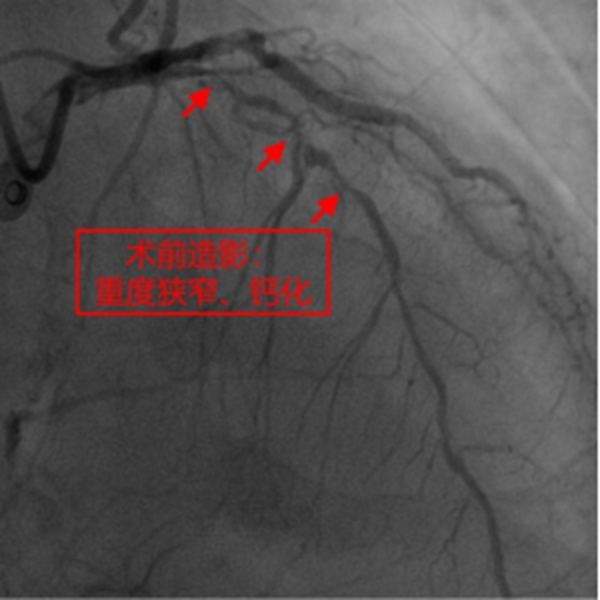

冉擘力主任介紹,患者為78歲男性,近年來常反復胸悶、氣短不適,合并心力衰竭、2型糖尿病、腎功能不全、貧血,多次因心力衰竭、肺部感染住院,不能正常生活。1月前患者曾行冠脈造影提示三支血管病變并對回旋支植入支架,但其中前降支嚴重鈣化伴重度狹窄,手術(shù)難度極大。冉擘力主任看到患者的造影結(jié)果后認為患者高齡、合并癥多、冠脈病變復雜,行外科冠脈搭橋風險較高,建議微創(chuàng)介入完成手術(shù),術(shù)前組織了全院多學科會診評估病情、討論圍術(shù)期治療方案。經(jīng)冠脈介入團隊崔坤副主任醫(yī)師、蒲云飛副主任醫(yī)師、王方超主治醫(yī)師多次討論,考慮冠脈彌漫性重度狹窄伴環(huán)形鈣化,決定采用Rota-Shock(旋磨+Shockwave)策略,處理冠脈彌漫且嚴重鈣化病變。

在征得患者及家屬同意,做好充分術(shù)前準備的情況下,冠脈介入團隊在冉擘力主任帶領(lǐng)下,按計劃給患者實施了血管內(nèi)超聲(IVUS)指導下經(jīng)皮冠脈旋磨+Shockwave沖擊波球囊碎裂鈣化斑塊及支架植入術(shù),術(shù)中團隊克服了一系列困難,最終安全順利地完成了全部介入手術(shù)過程,完全碎裂了環(huán)狀鈣化斑塊,效果非常滿意,歷時約1個多小時,手術(shù)成功,病人安返病房。術(shù)后患者胸悶、氣短明顯緩解,對治療效果十分滿意。